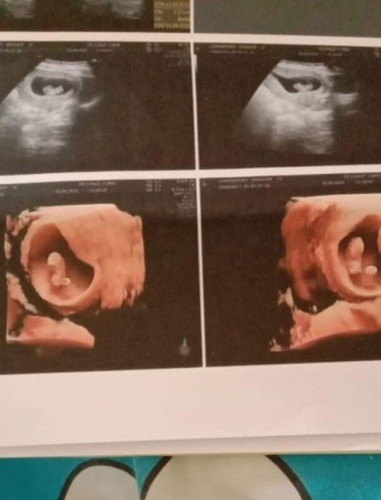

ดีจังเลยแม่ได้ซาวด์4มิติไวมาก